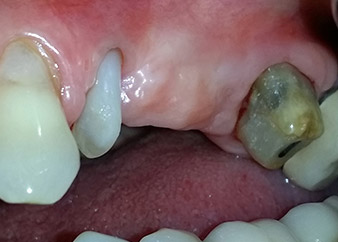

След един месец, в деня на операцията, болката и възпалението в зъб 24 е минимално, но подвижността в Miller class 2 е на лице. След отваряне на ламбата и почистването на периапикалната и перирадикуларната тъкани, обхватът на костния дефект стана очевиден (Фиг. 2 и 3).

В букалния корен, цялата вестибуларна и дистална кост липсва. Захващането е значително ограничено до палатиналния корен, подчертавайки предварително лошата прогноза. Зъб 27 също откри намалено хоризонтално захващане и минимално апикално разреждане (Фиг. 1) без клинични симптоми.

Въпреки това, ние се придържахме към първоначалния си план да запазим и двата зъба като абатмънти за временен мост по време на 6-месечната остеоинтеграция на имплантите. При повторна интервенция, ситуацията трябва да се преразгледа. Първо, в опит да се овладее ендо-перио проблема, останалата повърхност на зъба е внимателно обработена с пиезохирургично оборудване (Piezomed, W&H, използван с накрайник S1 под формата на шпатула, първоначално проектиран за ерозия на латералната синусна стена) (Фиг. 4).